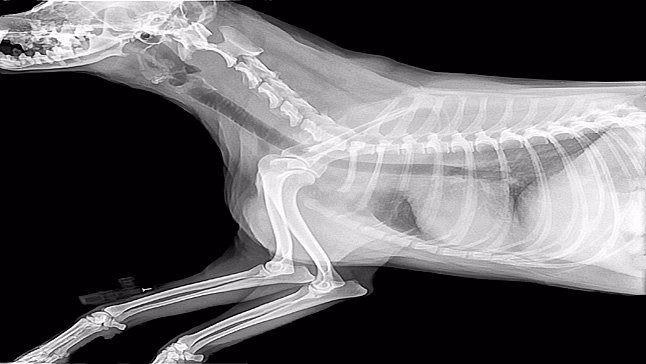

Estos problemas también se dan en otro tipo de enfermedades caninas, como la displasia de cadera. Por ello, es importante acudir al veterinario para que pueda hacer algunas pruebas radiológicas y darnos un diagnóstico. Si existen dudas es posible que el especialista también quiera hacer un T.A.C para ver si hay más patologías asociadas.

El tipo de cirugía dependerá del tipo de displasia de codo que se haya diagnosticado y de si hay una fragmentación leve o severa de los huesos y del cartílago a causa de la osteoartritis.